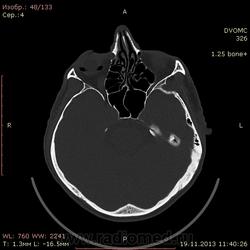

49 лет. Травма около месяца назад - удар в верхнюю челюсть спереди, так сказать...под нос.... в субнозальную область:-) Жалобы только на небольшие боли в месте травмы.

Воздух в правой орбите - под веком или нет? При моргании мог он так туда попасть и так распределиться? Или в резутьтате травмы из пазухи как-то попал и не уходит?

Мелкие пузырьки воздуха попадались, но такое количество и в виде кольца...Это нормально?

Это циркляжная лента для ретинопексии. Накладывают на глаз как пояс при отслойке сетчатки. Расспросите больного.

Огромное спасибо, никогда б не догадался...но подозревал, что что-то здесь не чисто. Завтра спрошу у пациента.